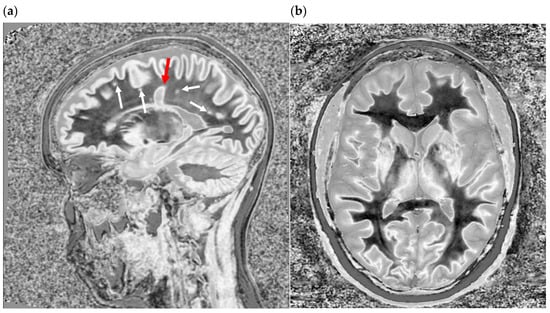

Figure 11.

Divided Subtracted Inversion Recovery (dSIR) in a patient with multiple sclerosis (MS). T2-FLAIR (left), inversion recovery (IR) T1-weighted (middle), and wide-domain dSIR with TIshort = 450 ms and TIlong = 850 ms (right) images through the pons in a patient with MS. A large plaque is obviously present in the left hemipons on the dSIR image (red arrow in the image on the far right). The contrast in this image is due to changes in white matter T1. The change in T1 is insufficient to cause noticeable contrast on the IR T1 image (middle). The change in T2 is insufficient to cause noticeable contrast on the T2-FLAIR image (left).

Figure 12.

Divided Subtracted Inversion Recovery (dSIR) in a patient with multiple sclerosis (MS). T2-FLAIR (left), inversion recovery (IR) T1-weighted (middle), and wide-domain dSIR with TIshort = 450 ms and TIlong = 850 ms (right) images through the upper corona radiata in a patient with MS. Three plaques are seen on the T2-FLAIR and IR T1 images (red arrows). More plaques are seen on the dSIR image (black arrows). The plaque in the left frontal white matter is seen on the dSIR image (yellow arrow) but, due to the high signal etching along its margins, could easily be mistaken for cortex.